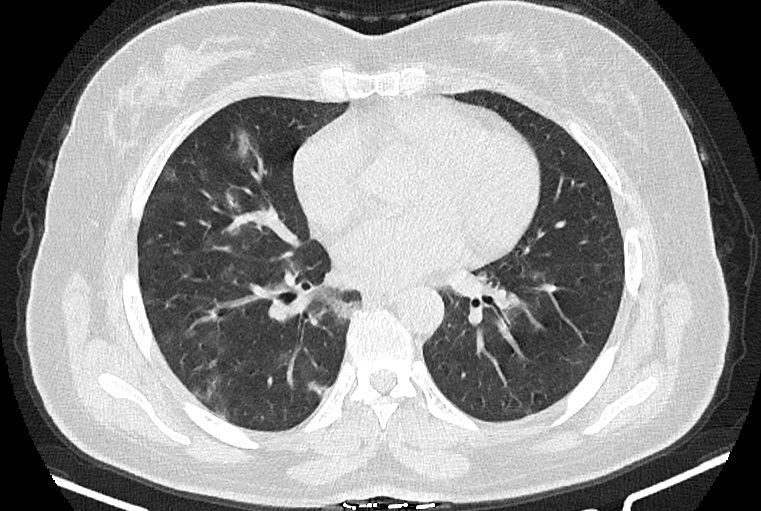

در HRCT از ريه ها(اسپيرال ، مولتي ديتکتور 16، مقاطع اگزيال با ضخامت 1mm بدون فاصله ) ، بدون كنتراست تزريقي :

-Ground glass opacities Patchy پراکنده در ريه ها مشهود است که مطرح کننده Viral pneumonia مي باشد . ( با درگيري 20 درصد حجم ريه )

-کلسیفیکاسیون دیواره آئورت و عروق کرونر ، تغییرات DJD در ستون فقرات ونشانه های CABG مشهود است .

نتیجه : Highly suggestive of COVID-19